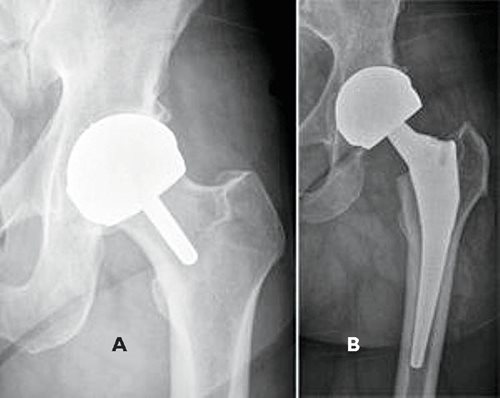

Traditional stemmed MoM hip replacements (and later resurfacings) were first introduced in the 1990s because they offered lower wear rates. For younger patients who need total hip replacement for osteoarthritis, longevity of the implant is a particularly important characteristic. It is estimated that since 1996, more than 1 million MoM implants have been inserted worldwide. MoM bearings can result from traditional hip replacement with a stemmed femoral prosthesis (Fig. 7B), or resurfacing of the femoral head with a metal cap (Fig. 7A), in which case more bone is preserved.

Fig. 7. Radiographs of metal-on-metal prosthesis.

A: Hip resurfacing prosthesis;

B: Stemmed metal-on-metal total hip replacement.

The benefits of MoM bearings compared with metal-on-polyethylene include not only lower volumetric wear rates, but also greater stability of the implant; because metal inserts are thinner than polyethylene liners, larger femoral head sizes can be used.

However, the use of MoM bearings in stemmed hip replacements is not recommended in the U.S. because there are reports in the literature of poor outcomes. When MoM bearings are inserted in patients who are more than 55 years old, have larger femoral heads, or have acetabular cups placed in excessive inclination, they have a higher risk of revision than polyethylene and ceramic bearings.